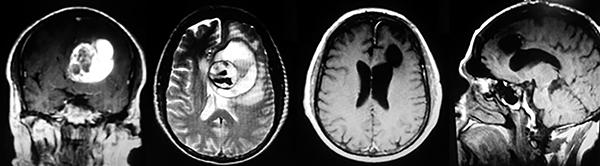

Figura 2:

Cortes axiales en ponderación T1, cambios postquirúrgicos.

EJEMPLO DE CASO CLÍNICO (9)

Paciente masculino de 34 años de edad, quien presenta crisis convulsivas parciales motoras de brazo y hemicara derecha, secundariamente generalizadas, posteriormente hemiparesia 4/5 para hemicuerpo derecho.

La TAC muestra un área hiperdensa a nivel frontal izquierdo heterogénea que no refuerza con medio de contraste.

LA RMN muestra una lesión bien circunscrita frontal parasagital izquierda con edema perilesional, hiperintensa en T1 y T2, de contenido sólido y quístico, con poca captación del medio de contraste.

Se realizó craneotomía frontal para abordaje interhemisférico anterior.

Se realiza resección total de la lesión de contenido hemático oscuro-verdoso, consistente en un angioma cavernoso. La RMN postoperatoria se observa solo la brecha quirúrgica sin evidencia de lesión.

En el postquirúrgico el paciente desarrollo síndrome frontal lateral, que se controló con Risperidona y remitió después de tres semanas, las crisis convulsivas remitieron y el medicamento se disminuyó de manera paulatina (figs. 4 y 5).

Figura 4:

Imágenes prequirúrgicas y postquirúrgicas de lesión multiloculada del caso 9.